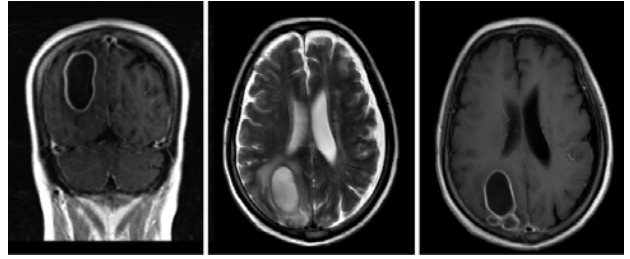

1 资料与方法患者,63岁男性,诊断“肾病综合征”10年余,长期口服激素治疗,病情反复发作。2019年11月8日因全身浮肿加重,伴头痛、视物模糊、四肢乏力、行走不能入院。入院时查体:T 36.8℃,P 63次/min,R 20次/min,BP 149/91 mmHg(1 mmHg=0.133 kPa),神志清,精神疲乏,全身浮肿。双侧瞳孔等圆等大,直径约2.5 mm,对光反射灵敏。双肺呼吸音粗,双肺未闻及干湿性啰音。心率63次/min,律齐,未闻及杂音。左上肢、双下肢肌力Ⅴ-级,肌张力正常;右上肢肌力Ⅳ级,肌张力升高。脑膜刺激征阴性,双下肢巴氏征未引出。四肢可见癣样皮疹。头颅CT(图 1)示右顶叶低密度灶,占位性病变。头颅增强MR(图 2)示右侧顶/枕叶多个囊性灶,考虑脓肿。入院后患者有反复发热,精神状态差,综合考虑右侧顶枕部脑脓肿,于2019年11月14日在全麻下行右侧顶枕部钻颅脑脓肿穿刺外引流术,术中抽取脓液培养阴性,予经验性使用万古霉素联合美罗培南抗感染治疗。术后患者依然反复高热,精神状态变差,考虑抗感染效果不佳。多次进行引流液及脑脊液培养均为阴性,经患者及家属同意后采集脑脊液进行二代基因测序(深圳华大基因科技有限公司,广东深圳),结果提示皮疽奴卡菌。诊断为原发性脑奴卡菌脓肿,予调整为复方磺胺甲噁唑口服,联合美罗培南静脉滴注,治疗2 d后体温逐步降低,意识状态好转。后期因家属因素,自动出院回当地治疗。本病例资料已获得患者知情同意。

| 图 2 患者入院时头颅MR |

本例患者为老年,有高血压病、心脏病、脑梗死等血管性基础疾病,因肾病综合征长期服用泼尼松治疗,存在免疫功能抑制,是中枢神经系统奴卡菌感染的高危人群。本例患者急性起病,出现发热、头痛、四肢乏力,四肢肌力轻度改变,头颅MRI增强和头颅CT表现为占位性病变,其临床表现和影像学与以往的报道[4-5]一致,并无明显特异性。在钻颅脑脓肿穿刺外引流术后,经验性强力抗感染方案(万古霉素联合美罗培南)未能奏效,多次的脓液和脑脊液培养均阴性,令临床诊治一度陷入困境。奴卡菌是革兰染色阳性杆菌,临床标本的检出率不高[6],其可能原因在于奴卡菌生长缓慢,甚至长达4周才出现阳性,远远超过常规培养观察周期。本病例在诊治陷入困境之时,脑脊液二代基因测序结果提示皮疽奴卡菌,为诊断和治疗提供可靠依据。二代基因测序技术作为一种新型诊断技术,能快速、准确地鉴定出微生物种属,明确病原学诊断[7-8],指导临床及时启动目标导向的微生物学治疗。对于临床难以检测、培养阳性率极低的病原微生物,如奴卡菌等,二代基因测序技术结果还可作为指导临床检测或培养方法的改进,延长实验室培养时间,从而提高传统方法阳性率[5, 7, 9]。